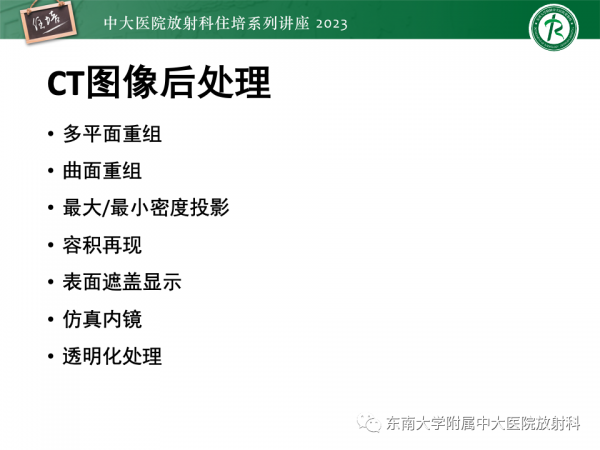

CT图像后处理

虽然到目前为止,诊断疾病还是以横断面显示的图像为主,但随着 CT 技术的发展,扫描中得到的数据不再是某一个或某几个层面的信息,螺旋 CT 的出现使得能够获得整个扫描范围内的容积信息。

16层及以上多层螺旋 CT 的出现导致轴方向上的分辨力大大提高,达到了各向司性体素的要求,从而极大地促进了CT后处理技术的发展。

多层螺旋CT检查中得到的数据量成倍增加,如何方便快捷地显示所得到的大量数据,也需要CT后处理技术的发展为此大量信息的显示提供帮助。

所谓CT后处理技术即是指在扫描完成影像获取以后,利用计算机功能对所采集一定范围的三维容积数据进行处理,改善图像质量或有目的地选择显示其中所关心的内容。

可以根据组织不同、观察目的不同选择相应的算法

CT图像后处理

虽然到目前为止,诊断疾病还是以横断面显示的图像为主,但随着 CT 技术的发展,扫描中得到的数据不再是某一个或某几个层面的信息,螺旋 CT 的出现使得能够获得整个扫描范围内的容积信息。

16层及以上多层螺旋 CT 的出现导致轴方向上的分辨力大大提高,达到了各向司性体素的要求,从而极大地促进了CT后处理技术的发展。

多层螺旋CT检查中得到的数据量成倍增加,如何方便快捷地显示所得到的大量数据,也需要CT后处理技术的发展为此大量信息的显示提供帮助。

所谓CT后处理技术即是指在扫描完成影像获取以后,利用计算机功能对所采集一定范围的三维容积数据进行处理,改善图像质量或有目的地选择显示其中所关心的内容。

可以根据组织不同、观察目的不同选择相应的算法